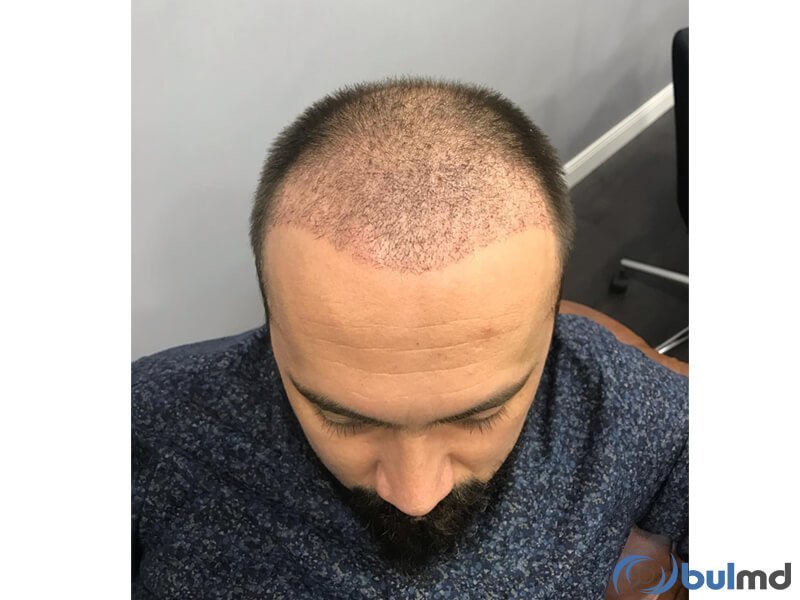

About BulMD (Bul Medical Consulting and Tourism Company) BulMD are a dedicated team of professionals, who work tirelessly with doctors and medical professionals, in order to provide our patients with the best treatment options with world-class assistance, facilities and care possible. We know how difficult it is to choose the best limb lengthening surgeon, hair transplant clinic, or obesity treatment center. To make this decision maki... (Show more)